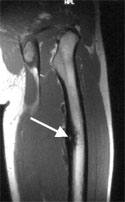

Imaging usually is very typical: X-rays show new bone formation and sometimes a small lucent spot (smaller than 1.5 cm), which is defined as the nidus. Computed tomography (cat scan, CT) is even better suited to show the new bone formation and the nidus. Because there may be a lot of inflammatory swelling and edema in the bone and soft tissues around the tumor magnetic resonance imaging (MRI) may sometimes be difficult to interpret and CT may be required to further assess these tumors. Radionuclide or bone scans show increased uptake of the radioactive tracer, this may sometimes be very focal.

Magnetic resonance image of an osteoid osteoma of the thigh (femur). Increased bone formation (dark) surrounding a brighter spot representing the nidus (arrow) of the osteoid osteoma.